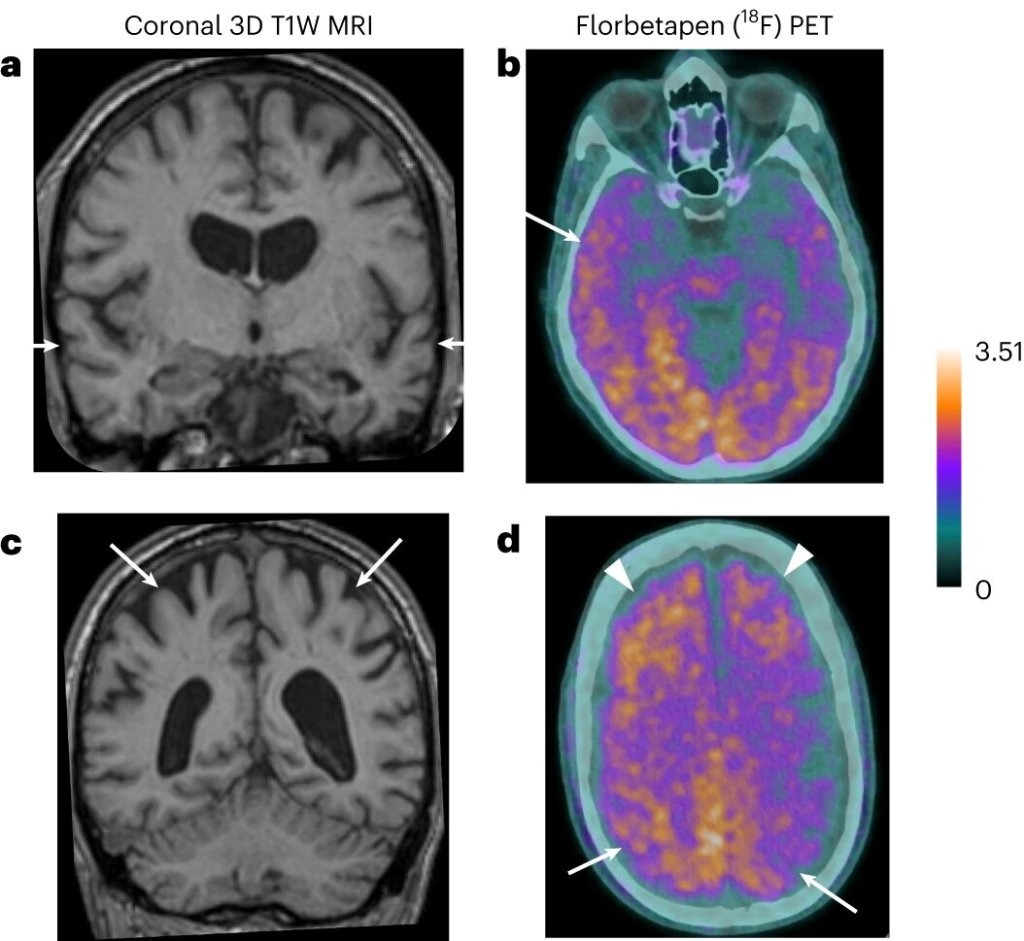

Se cree que la enfermedad es provocada por la acumulación de proteínas, como la proteína beta amiloide en el cerebro. Esto provoca placas que alteran las funciones cerebrales, afectando, en principio, a la memoria y, más tarde, a áreas que controlan el lenguaje y el comportamiento social.